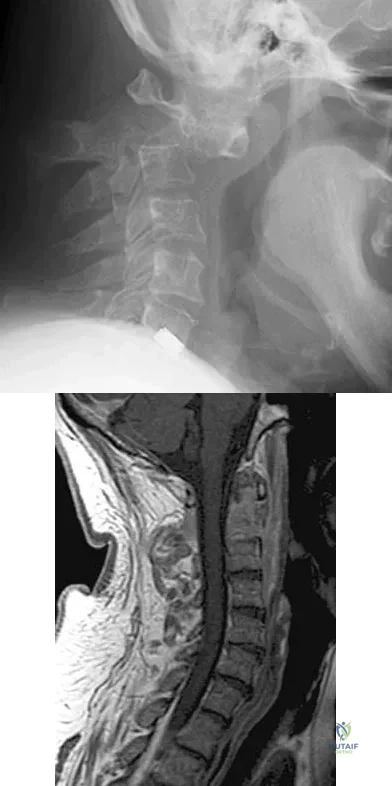

Figures 5a and 5b show the radiograph and MRI scan of a patient who has severe mechanical neck pain but no neurologic problems. Biopsy and work-up show the lesion to be a solitary plasmacytoma. Treatment should consist of

Explanation

Figures 23a and 23b show the MRI scans of a 50-year-old woman who has increasing gait disturbance. She reports three falls in the past week. Examination reveals hyperreflexia, motor weakness in the biceps and triceps, and a positive Hoffman's sign. What is the most appropriate treatment plan?

Explanation